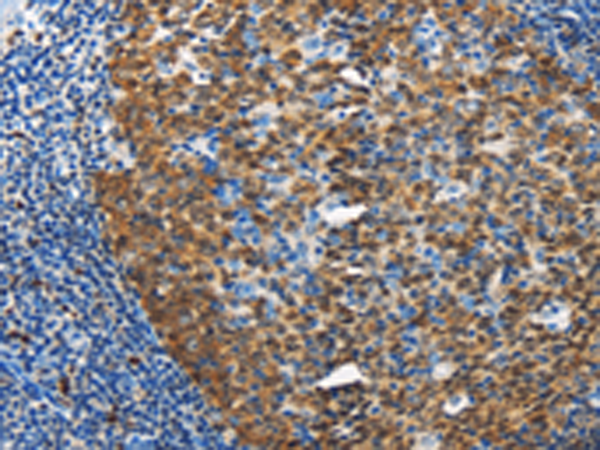

分类: 科研抗体货号: P07998别名: M6A; GPM6应用: WB,IHC反应种属: Human, Mouse, Rat